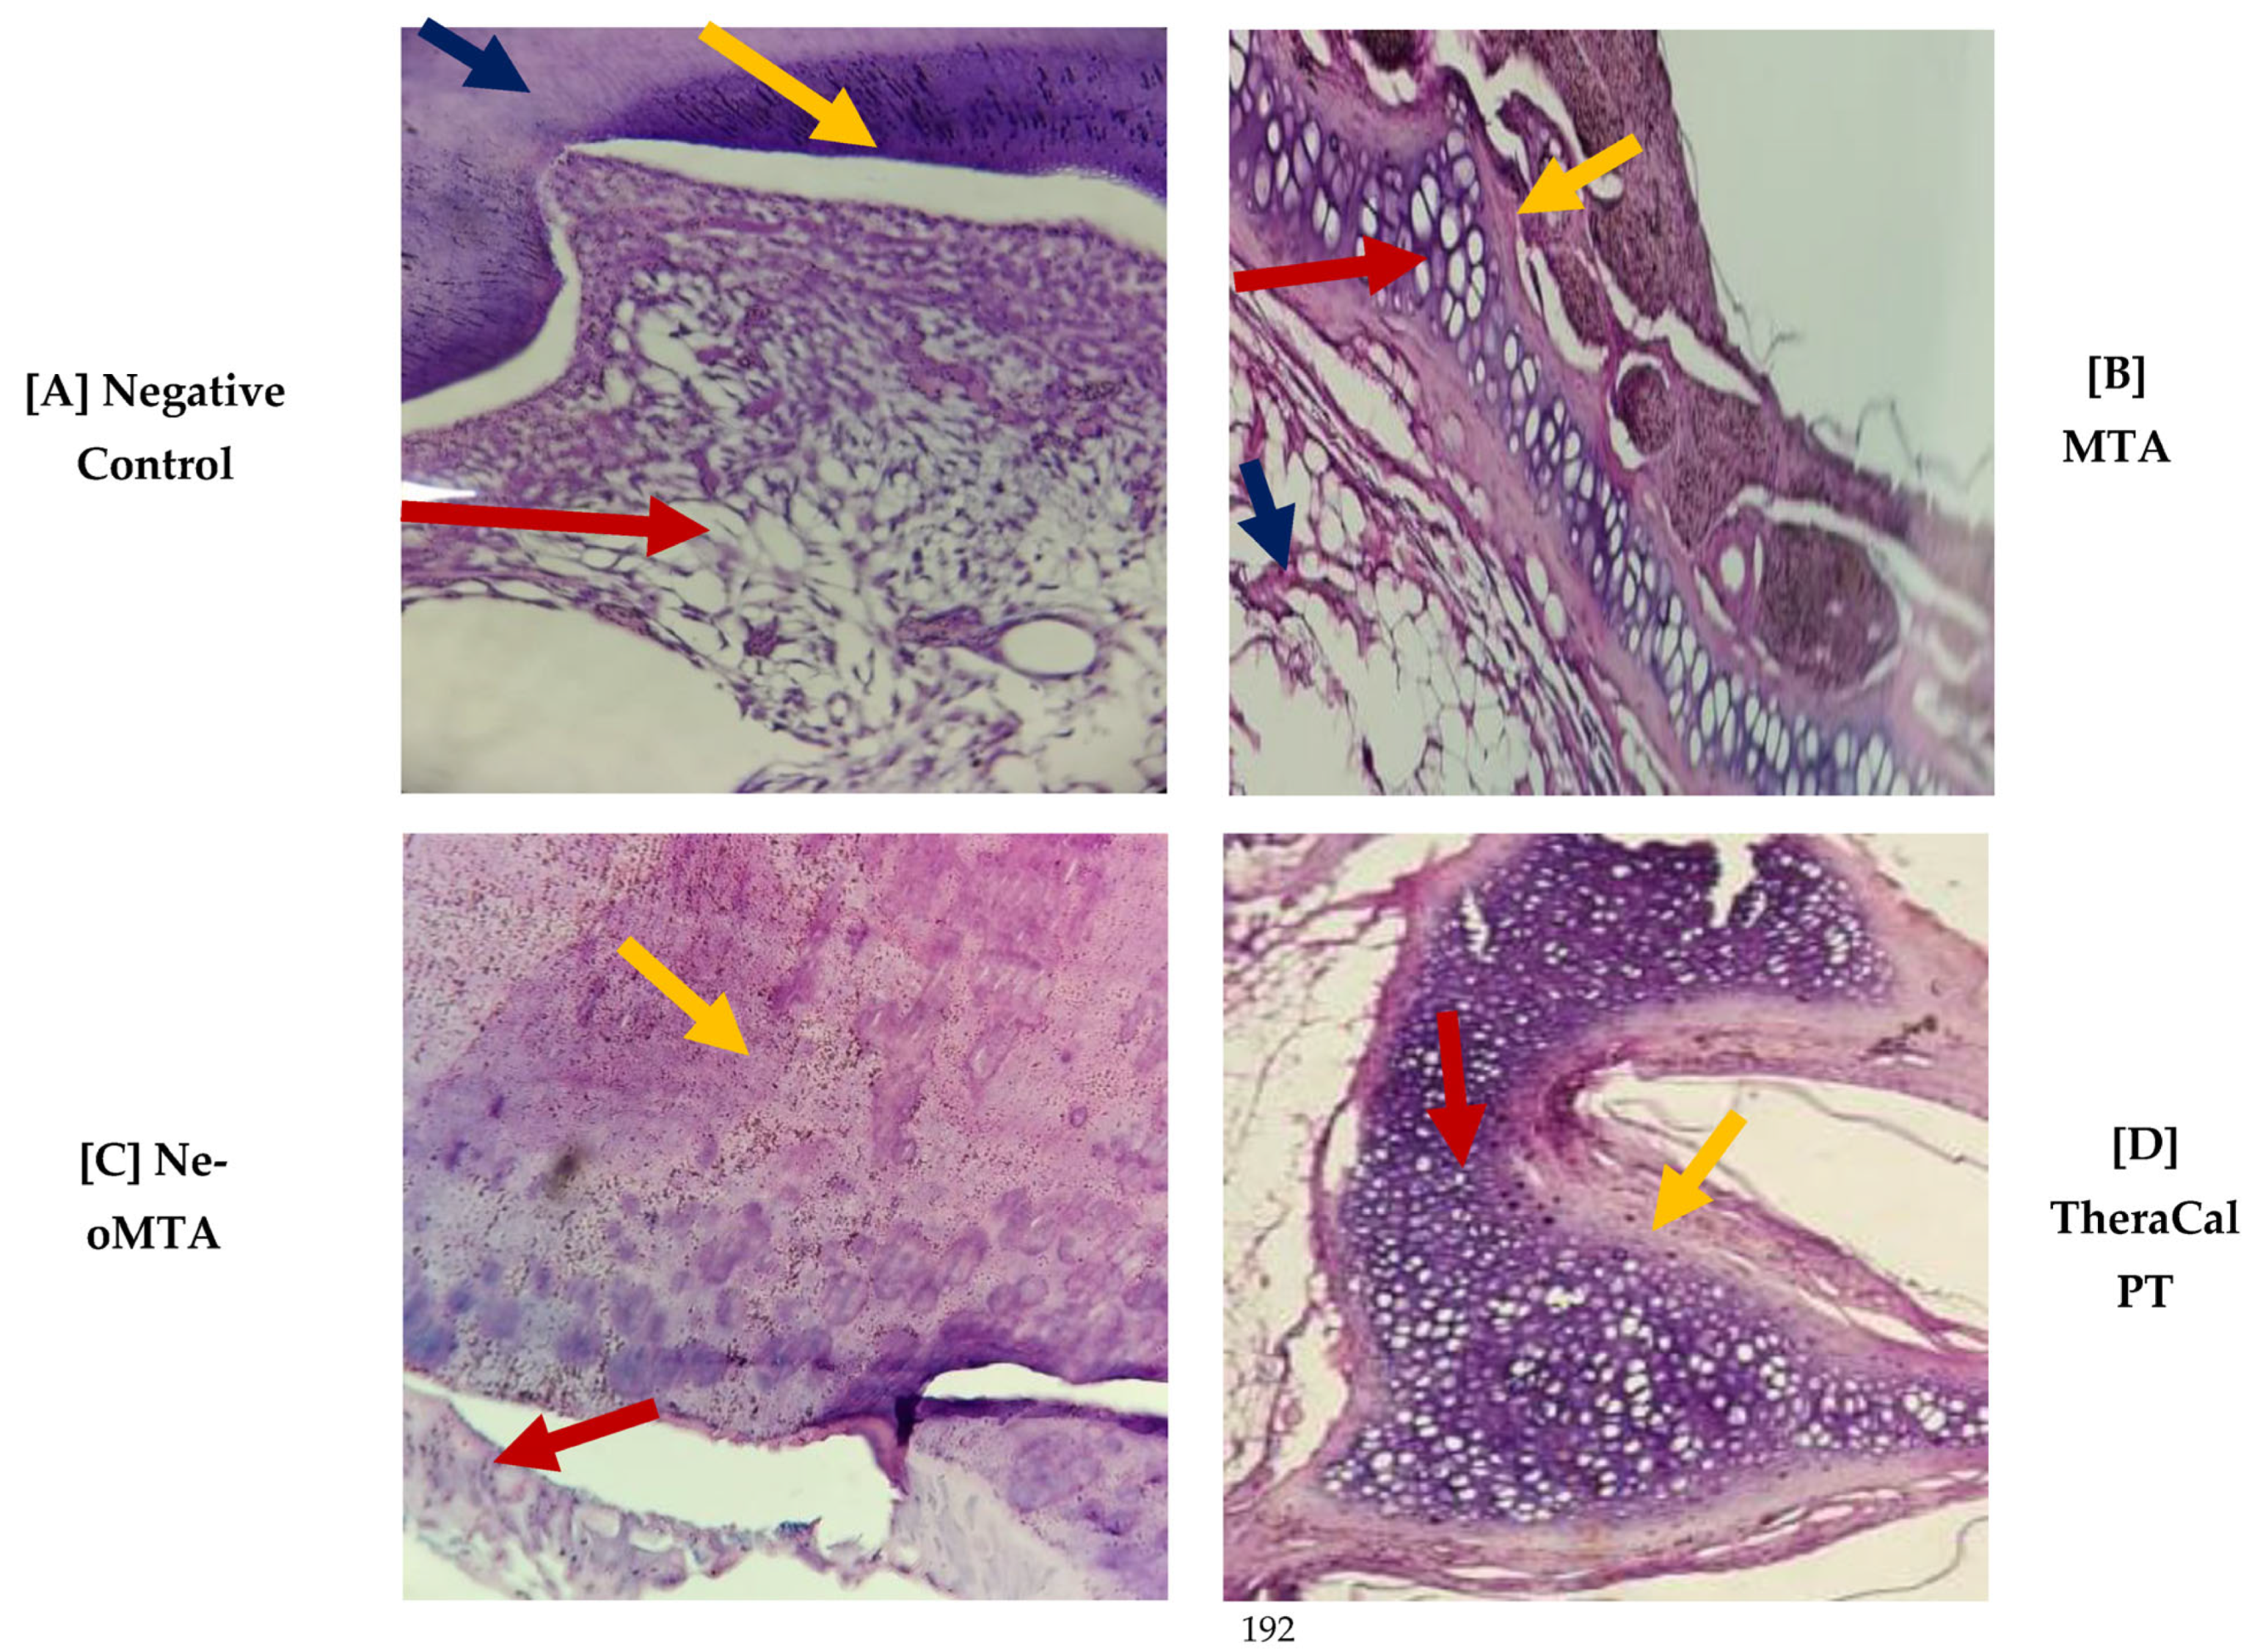

Figure 5. Photomicrograph of Group 3 (45 days) cross-sections stained with H&E. (A) at 4×, (B) 40×, (C) 10× and (D) at 40×.

(A)

The stellate epithelium of the dental pulp (red arrow) and the surrounding odontoblastic layer (yellow arrow) and dentin (blue arrow) were observed.

(B)

The particulate dental material was observed in the form of a cobweb with a basophilic color that was more purple than the rest of the tissues (red arrow); there was the presence of a pseudocapsule of surrounding fibroconnective tissue that was loose and fibrous (yellow arrow, and the presence of adipose tissue (blue arrow).

(C)

Disorganization of the odontoblast layer was observed and adjacent to it there was a cobweb of basophilic epithelium that corresponded to the material and showed us that there was an integration with the dentin (red arrow).

(D)

Disorganization of the odontoblastic layer was observed and adjacent to it we found the presence of a cobweb of basophilic epithelium that corresponded to the dental material being tested, where there was also an integration with the dentin (red arrow).

With regard to pulp-tissue disorganization (Figure 3), in the negative control the presence of this variable was not observed (15, 30, and 45 days). On the other hand, in MTA Angelus, NeoMTA, and TheraCal PT, there was grade-1 pulp-tissue disorganization. In terms of statistics, statistically significant differences were not observed with a p of >0.05 (Figure 4). Likewise, in the formation of reparative dentin (Figure 5), in the negative control there was no presence of this, but in the three materials utilized, a grade-1 result was revealed, with a final result of statistically significant differences not being observed (p > 0.05) (Figure 6).